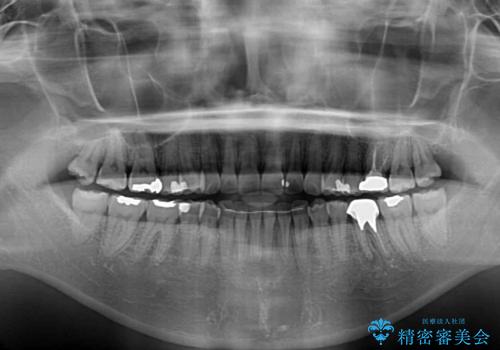

- 前歯のデコボコと上下スペースと前歯の隙間を気にして来院された患者様です。

目立たない装置を希望とのことでインビザラインにより、デコボコを解消しつつ、上下の前歯の隙間を閉じていくこととしました。

デコボコはあっという間に解消されましたが、上下前歯の隙間がなかなか解消されませんでした。

飲み込みの際に舌を前方に突出する癖があり、飲み込みの度に前歯に強く接触していたため、上下前歯の隙間が維持されていました。

舌の訓練を徹底していただいたことで、徐々に隙間は解消され、きれいな歯列に整えることができました。